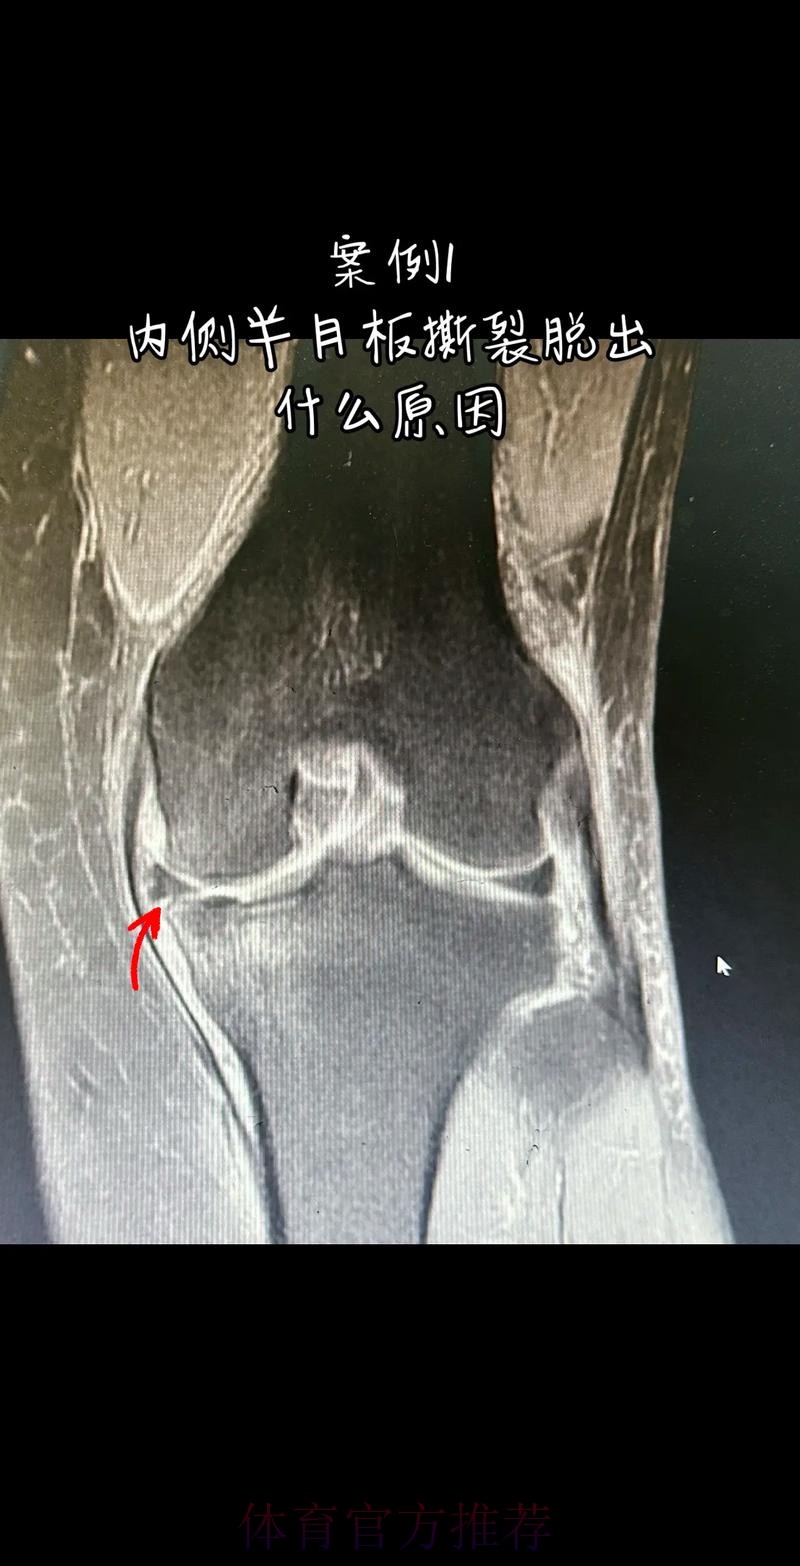

官方:阿拉巴左膝内侧半月板撕裂 预计伤缺6-8周